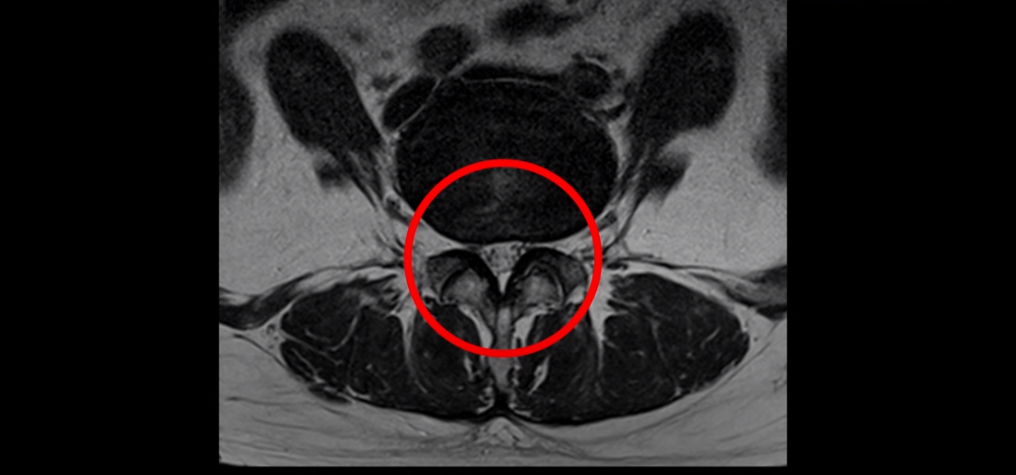

3번 4번과 4번 5번에 중심성 협착이 있는데

4번 5번이 더 심합니다.

또 4번 5번 마디에 오른쪽으로 찢어져서 밀려나온 디스크 탈출이 보입니다.

밀려나온 수핵이 조금 흘러내려 있습니다.